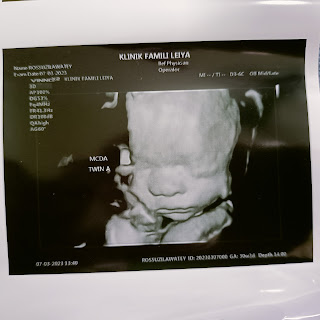

ini Scan kali 4.. masa ni kat private..

Ini scan masa 11 minggu 5 hari . 25 Nov 2022